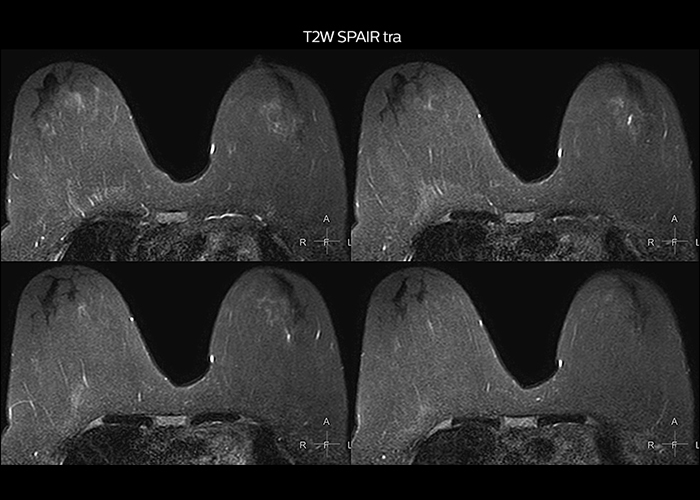

“On average, we scan about 80 patients per day, but on some days we scan well over 100 patients. The scanner is in use 7 days per week, operated 20 hours per day on week days and 8 hours per day in the weekend,” Mr. Tuna says. “To avoid coil changes we plan examinations of similar anatomies back to back, such as head and spine. Multiva helps us here a lot because coils don’t need to be changed frequently. Moreover, thanks to parallel imaging technology and 16-channel HeadSpineTorso and 8-channel MSK coils we are able to achieve excellent image quality. In this way Multiva helped us to increase both image quality and productivity.” “Neurological cases, such as brain and spine imaging, represent the largest share in our MR scanning, followed by musculoskeletal cases. In general, we use simple and basic imaging protocols. But occasionally, we use advanced techniques for problematic cases if necessary.

“Since we have Multiva, we have improved our workflow, because it has been so easy for our operators to learn and use Multiva. Our operators notice that the coils are lightweight and coils don’t need to be changed frequently. The user interface is easy to use. Features like this help us to scan a high number of patients. For instance, the musculoskeletal coils can be used interchangeably, and due to the user-friendly interface, the number of mistakes such as, for example, correct coil element selection has decreased significantly, because the system does it automatically by itself.” “Most important, Multiva satisfies our clinical imaging needs very well,” says Mr. Tuna. “Many features of Multiva have become similar to the Ingenia system. Even in more complex imaging such as abdominal and cardiac, the image quality and performance of Multiva is better than we expected. General surgeons and physicians from our hospital’s internal medicine department prefer to refer to us because of this.”